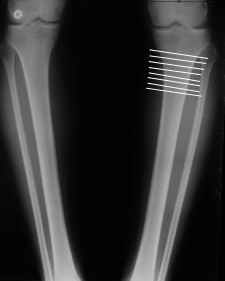

Или давай для простоты я картинку с несколькими вариантами прилагаю, которая линия, если считать сверху, тут оптимальна с высоты твоего немалого опыта? И имеет ли значение, как сечь - параллельно суставной щели, перепендикулярно диафизу или иначе как-то?

Мне представляется оптимальным на уровне 3-4 линии (т.е. как раз посредине отмеченной зоны). Если рассчимтываешь делать медиализацию, то параллельно суставной поверхности, иначе просто не сдвинешь без джистракции - отломки зацепятся. Если без медиализации - то вообще не имеет значения.